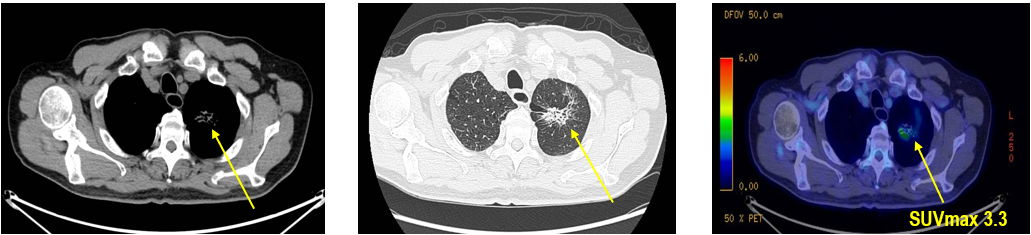

CT及PET-CT随访(2023年11月、2024年1月):评估新辅助治疗效果,右下肺叶肿块缩小,右肺门淋巴结代谢活性消失,右肺上叶结节稳定但代谢活性降低,左肺上叶及双侧磨玻璃样病变稳定。

手术治疗:2024年1月行右肺下叶切除术及右肺上叶楔形切除术,术中病理显示右肺下叶为腺癌伴SCLC灶,右肺上叶为腺癌。术后病理分期:右肺下叶腺癌为ypT2aN0M0(IB期),伴SCLC灶,考虑为治疗后转化;右肺上叶腺癌为ypT1bN0M0(IA2期)。